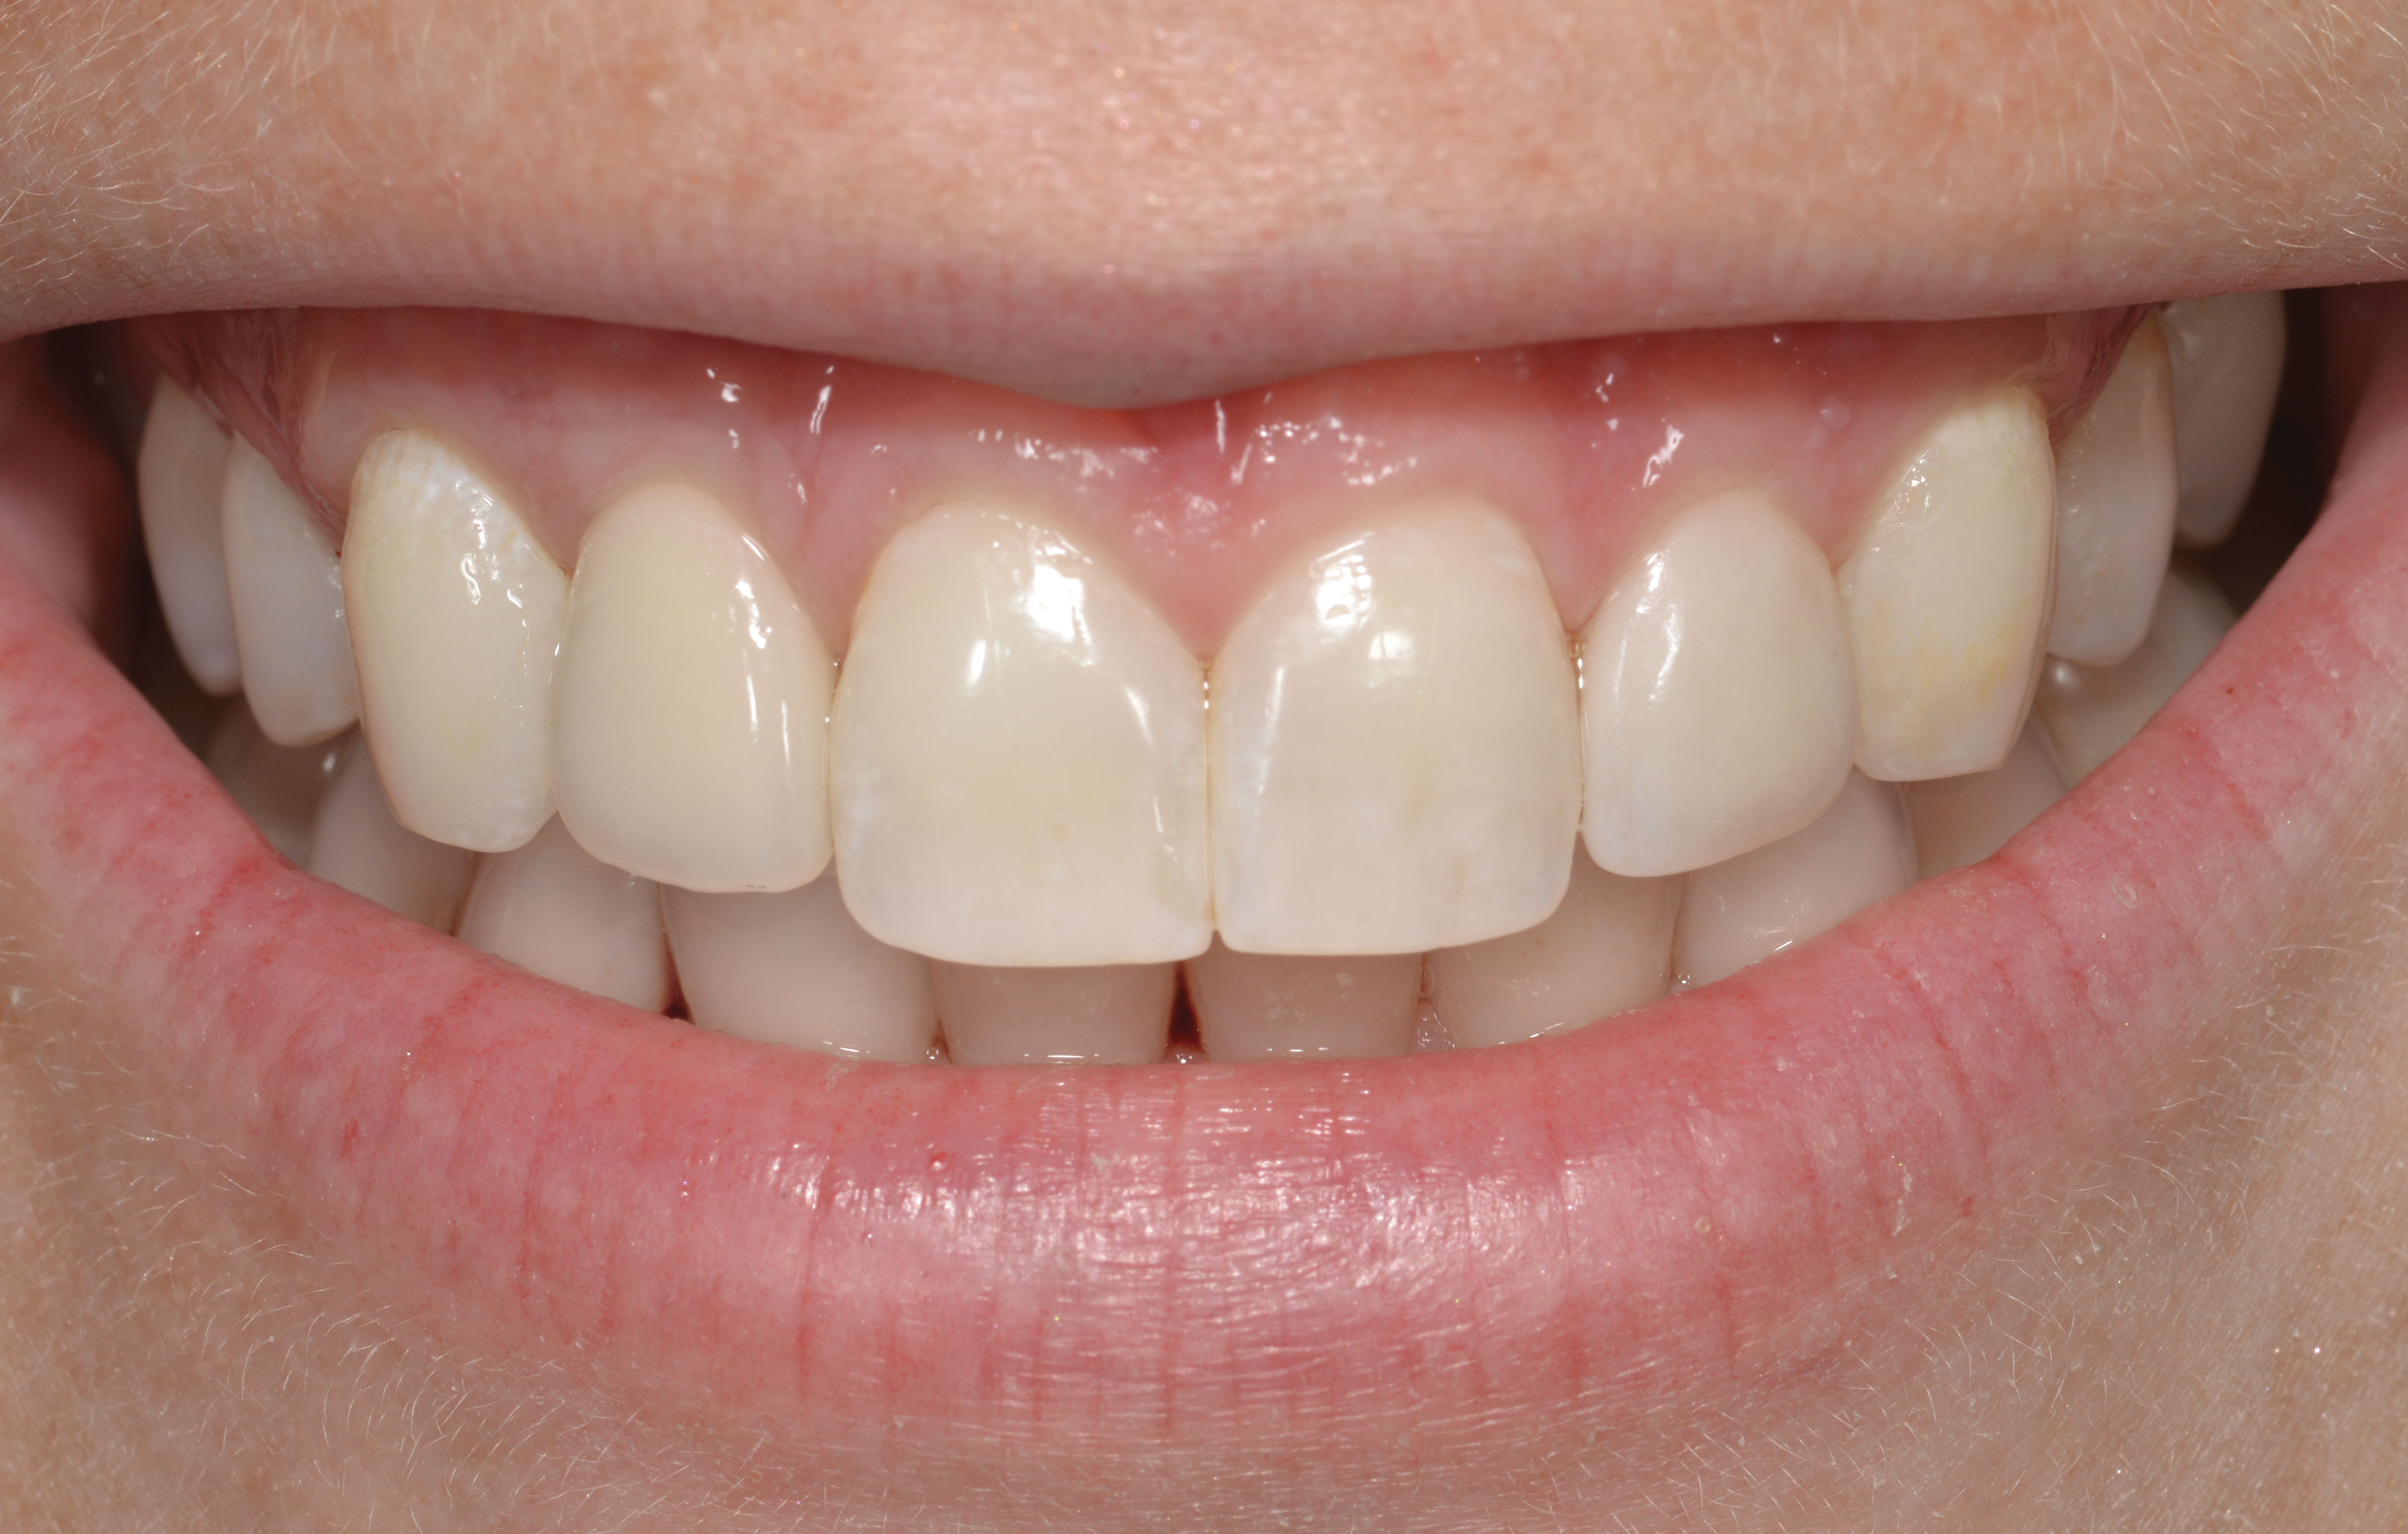

Fig 45. The definitive crown tooth No. 26 seated in place and provisionally cemented. The recession defect was eliminated with the removal and replacement of a new implant in the proper position.

Figure 45

Fig 46. The post-treatment radiograph showing a healthy stable implant and restoration.

Figure 46